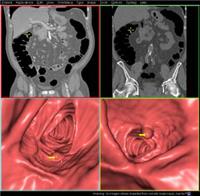

结肠肿瘤临床上的诊断

镜检时不仅可以发现肿瘤肿,还可观察其大小、位置以及局部浸润范围。通过乙状结肠镜可以采取组织作病理检查。纤维结肠镜检查可提[详细]